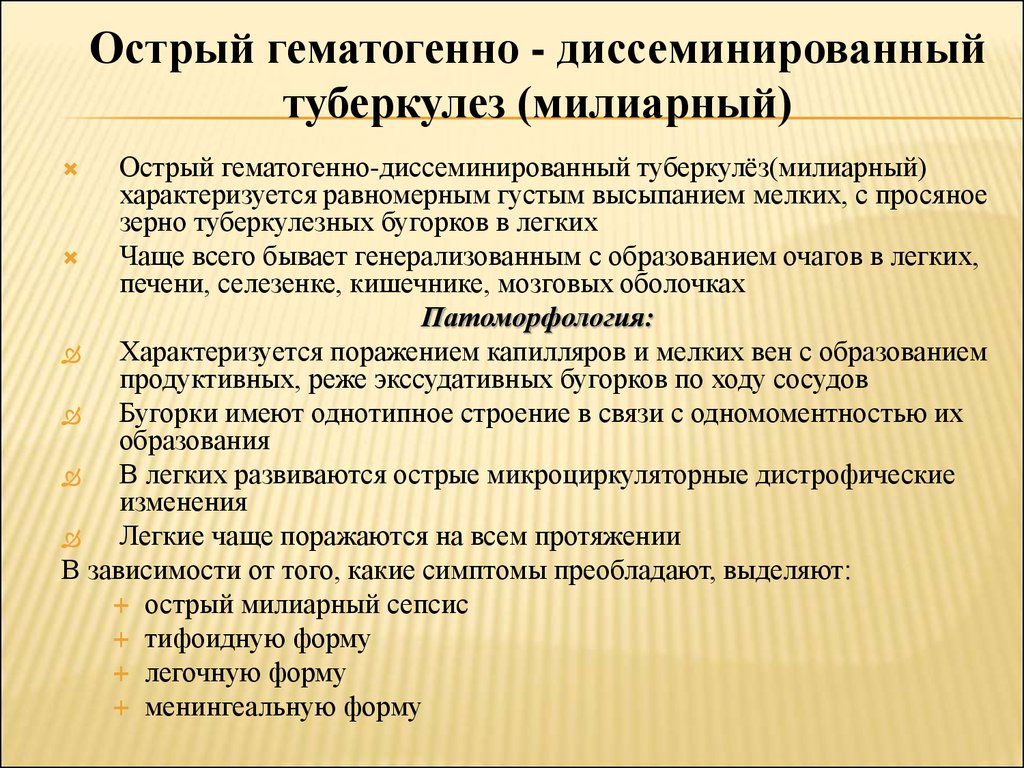

В клинической картине острого гематогенно диссеминированного туберкулеза преобладает